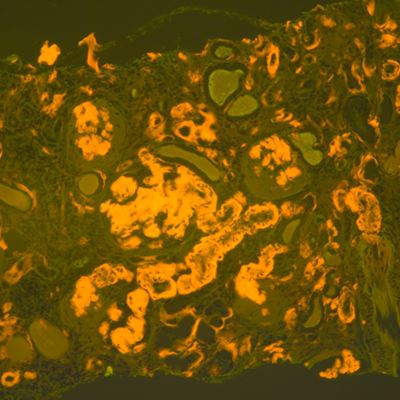

Amyloidosis is a rare but serious disease caused by the buildup of abnormal amyloid deposits in the body. The new guideline aims to support earlier and more accurate diagnosis, which is critical for effective treatment but has often been challenging for laboratories and pathologists.

• Congo Red Stain: Remains the standard for amyloid detection; other stains should be validated.

• Fluorescence Microscopy: May improve Congo red sensitivity where available.